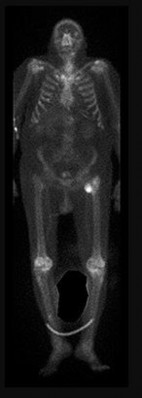

A 12-year-old boy presents with left thigh pain, an antalgic gait, and an externally rotated left lower extremity. Radiographs demonstrate the pathology shown. Which of the following is considered an absolute indication for prophylactic pinning of the asymptomatic, contralateral hip in a patient presenting with Slipped Capital Femoral Epiphysis (SCFE)?

Correct Answer: Underlying endocrine disorder (e.g., hypothyroidism)

Explanation:

SCFE is characterized by a displacement of the proximal femoral epiphysis. Prophylactic pinning of the contralateral hip is somewhat controversial but generally recommended in patients with a high risk of subsequent contralateral slip. Absolute indications or highly strong recommendations for prophylactic contralateral pinning include an underlying endocrine disorder (such as hypothyroidism or growth hormone deficiency), renal osteodystrophy, previous radiation therapy, and presentation at a very young age (e.g., < 10 years). Endocrine disorders dramatically increase the risk of bilateral involvement, often occurring simultaneously or sequentially.